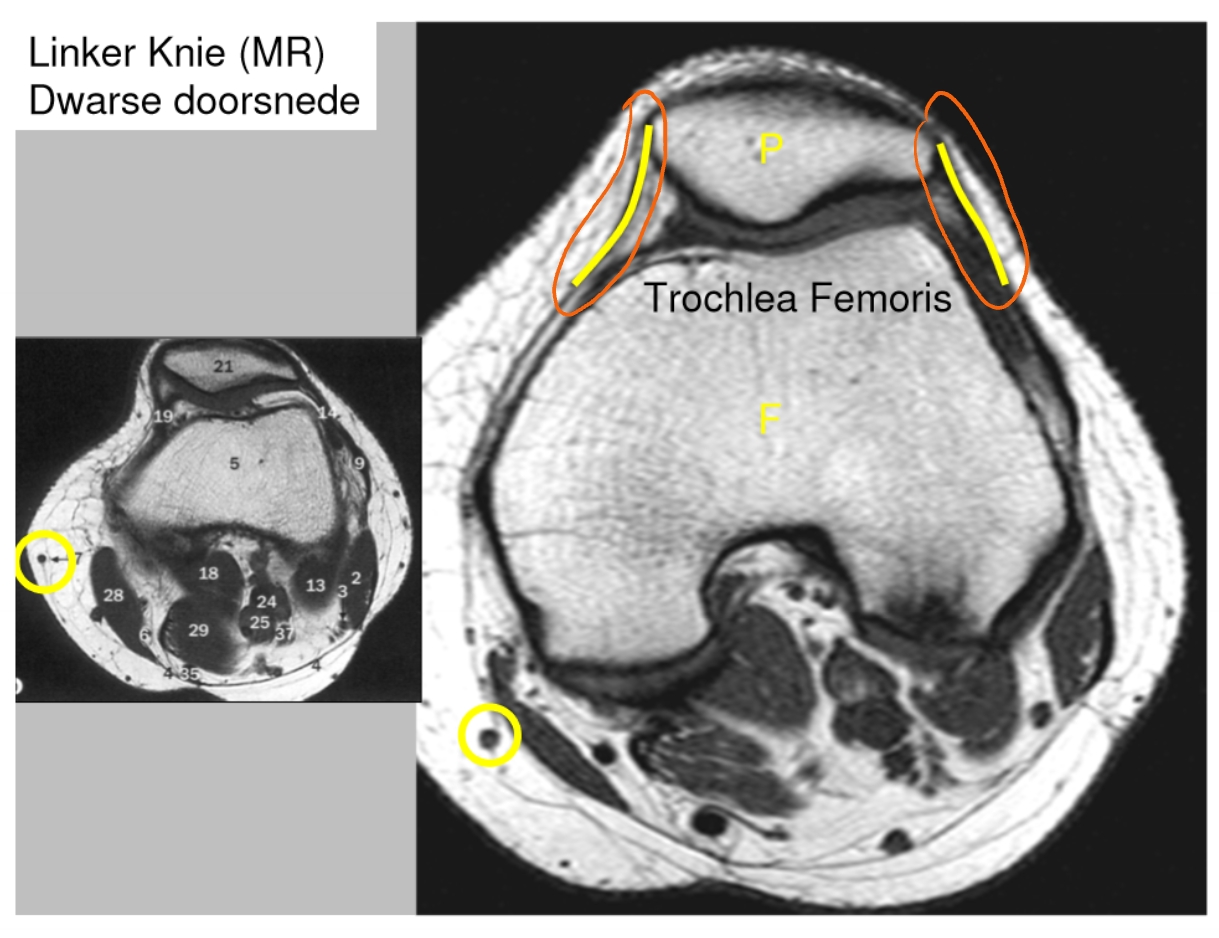

→ linker knie (MR): dwarse doorsnede

meniscus

anterieur

posterieur

pees van de m. quadriceps

patellapees

vetweefsel van Hoffa

voorste kruisband

achterste kruisband

meniscus (anterieur)

meniscus (posterieur)

tractus iliotibialis

mediaal collateraal ligament

lateraal collateraal ligament

→ linker knie (MR): coronale doorsnede